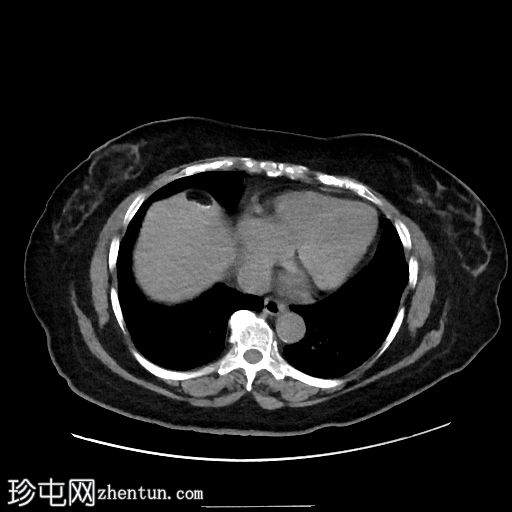

轴位

平扫

肝脏VIII段可见边界清晰的含液和脂肪的病变,边缘可见钙化,符合卵巢畸胎瘤肝包膜沉积。

腹盆腔可见较大的规则、薄壁病变,主要为液体,内部可见含脂肪的小叶和边缘钙化,符合卵巢畸胎瘤的影像学表现。